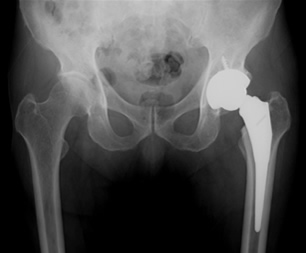

また70歳以下や比較的活動性の高い方には前記のような人工骨頭置換術ではなく全人工関節置換術(図3)を主に前方アプローチ(DAA)で行っています。全人工股関節置換術後の多くの方は退院まで一貫して当院でリハビリを行っており受傷以前の生活にかなり近づけることができています。

図3-1

大腿骨頸部骨折 人工股関節置換術前

図3-2

全人工股関節置換術後

図3-1

大腿骨頸部骨折 人工股関節置換術前

図3-2

全人工股関節置換術後

骨折箇所に人工骨を置換します。図3-2のレントゲンで白く写っているのは人工骨です。

変形性股関節症

変形性股関節症は一次性(加齢や過負荷)と二次性(臼蓋形成不全や先天性股関節脱臼)によるものがあり本邦ではほとんど二次性です。変形性膝関節症よりは発症数は少ないですが関節軟骨の変性・摩耗は同様で骨変形もきたします。まずは投薬、運動療法などの保存療法を行い、症状の軽快が得られない場合は活動量や年齢を考慮して主に前方アプローチ(DAA)にて全人工股関節置換術(図5)を行っています。術後も多くの方が退院まで当院で一貫してリハビリをされています。

図5-1

変形性股関節症

図5-2

全人工股関節置換術後

図5-1

変形性股関節症

図5-2

全人工股関節置換術後